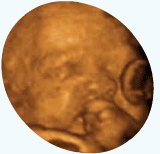

从孕育的第一刻起,妈妈的新就与宝宝一起跳动:记录生命最初的感动,见证生命的奇迹,从四维彩超开始!

360°立体展示胎儿健康